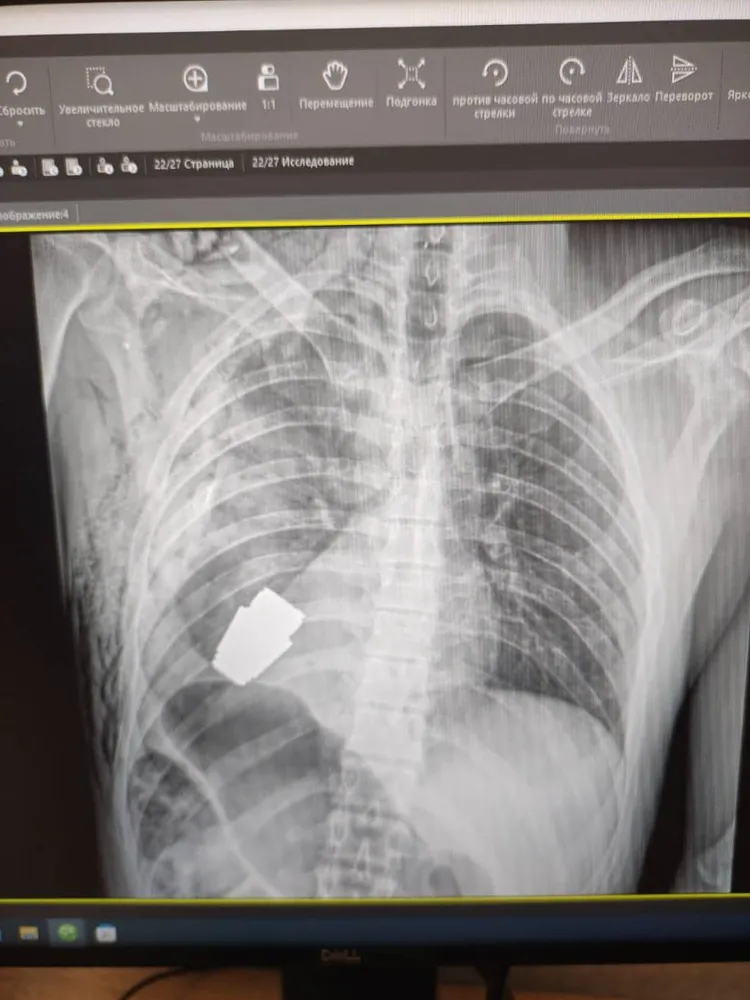

美國福斯新聞網(Fox News)13日報導,烏克蘭國防部副部長馬利亞爾(Hanna Maliar)本月9日在個人臉書專頁發布一張X光照片,病患胸口位置有一個外來物體,馬利亞爾指出那是一枚未爆炸的VOG手榴彈。

馬利亞爾表示,X光照片中是一名不具名的28歲烏克蘭士兵。由於手榴彈隨時可能爆炸,烏克蘭最有經驗的外科醫生,在未使用電燒的情況下操刀手術的;電燒是利用電流的熱能,使出血的血管凝固,以達到止血的手術技術。

手榴彈未爆炸的部分卡在該名士兵心臟下方。翻攝臉書

烏克蘭內政部顧問格拉申科(Anton Gerashchenko)則在可加密社群網站Telegram發文指出,手榴彈未爆炸的部分卡在該名士兵心臟下方。

手術期間由兩名工兵或軍事工程師在場監督,以確保醫務人員的安全。

格拉申科表示,手術相當成功,這名傷兵後來被送至康復中心,情況穩定。